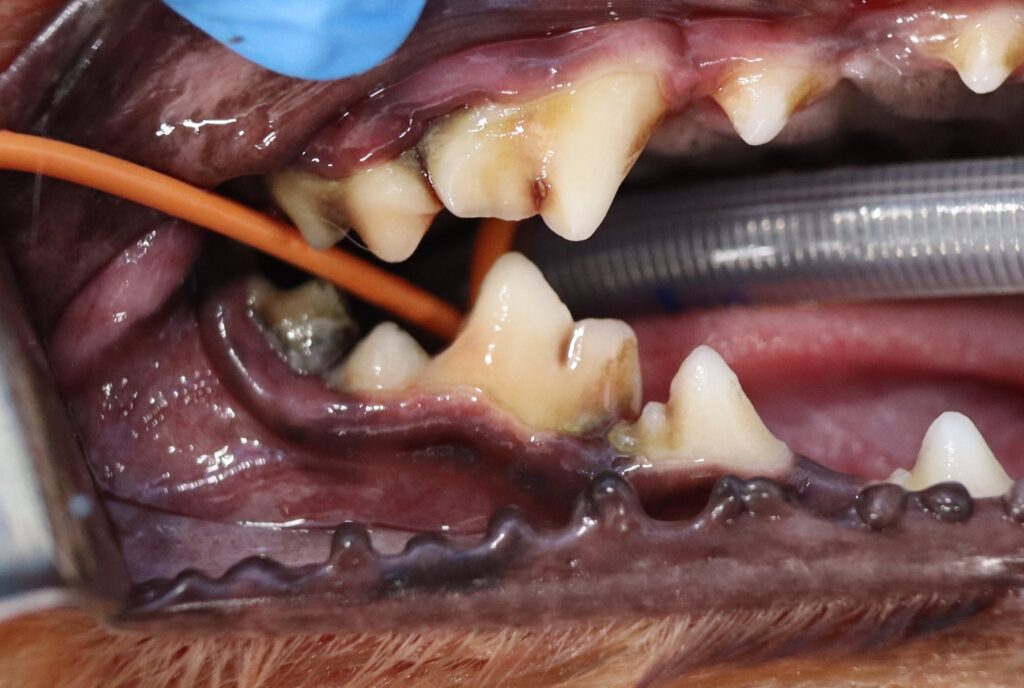

視診で観察してみると、下顎第一後臼歯周辺にプラークの沈着を認め、歯周ポケットを測るプロービング検査では基準値を超える深さのポケットが確認されました。

一見すると大きな異常はなく、歯も綺麗に見えます。飼い主さまも驚かれていましたが、全身麻酔下での歯科用レントゲンで右下顎第一後臼歯に進行した歯周病が確認されました。